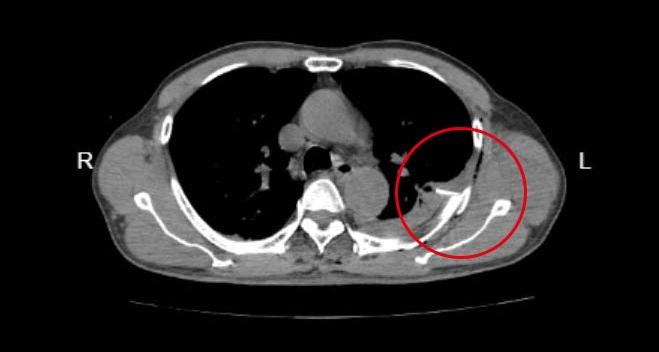

创伤中心迅速启动绿色通道,结合胸部CT,发现患者除肋骨骨折外,还合并胸壁皮下气肿。

急诊胸部CT:左侧多发肋骨骨折